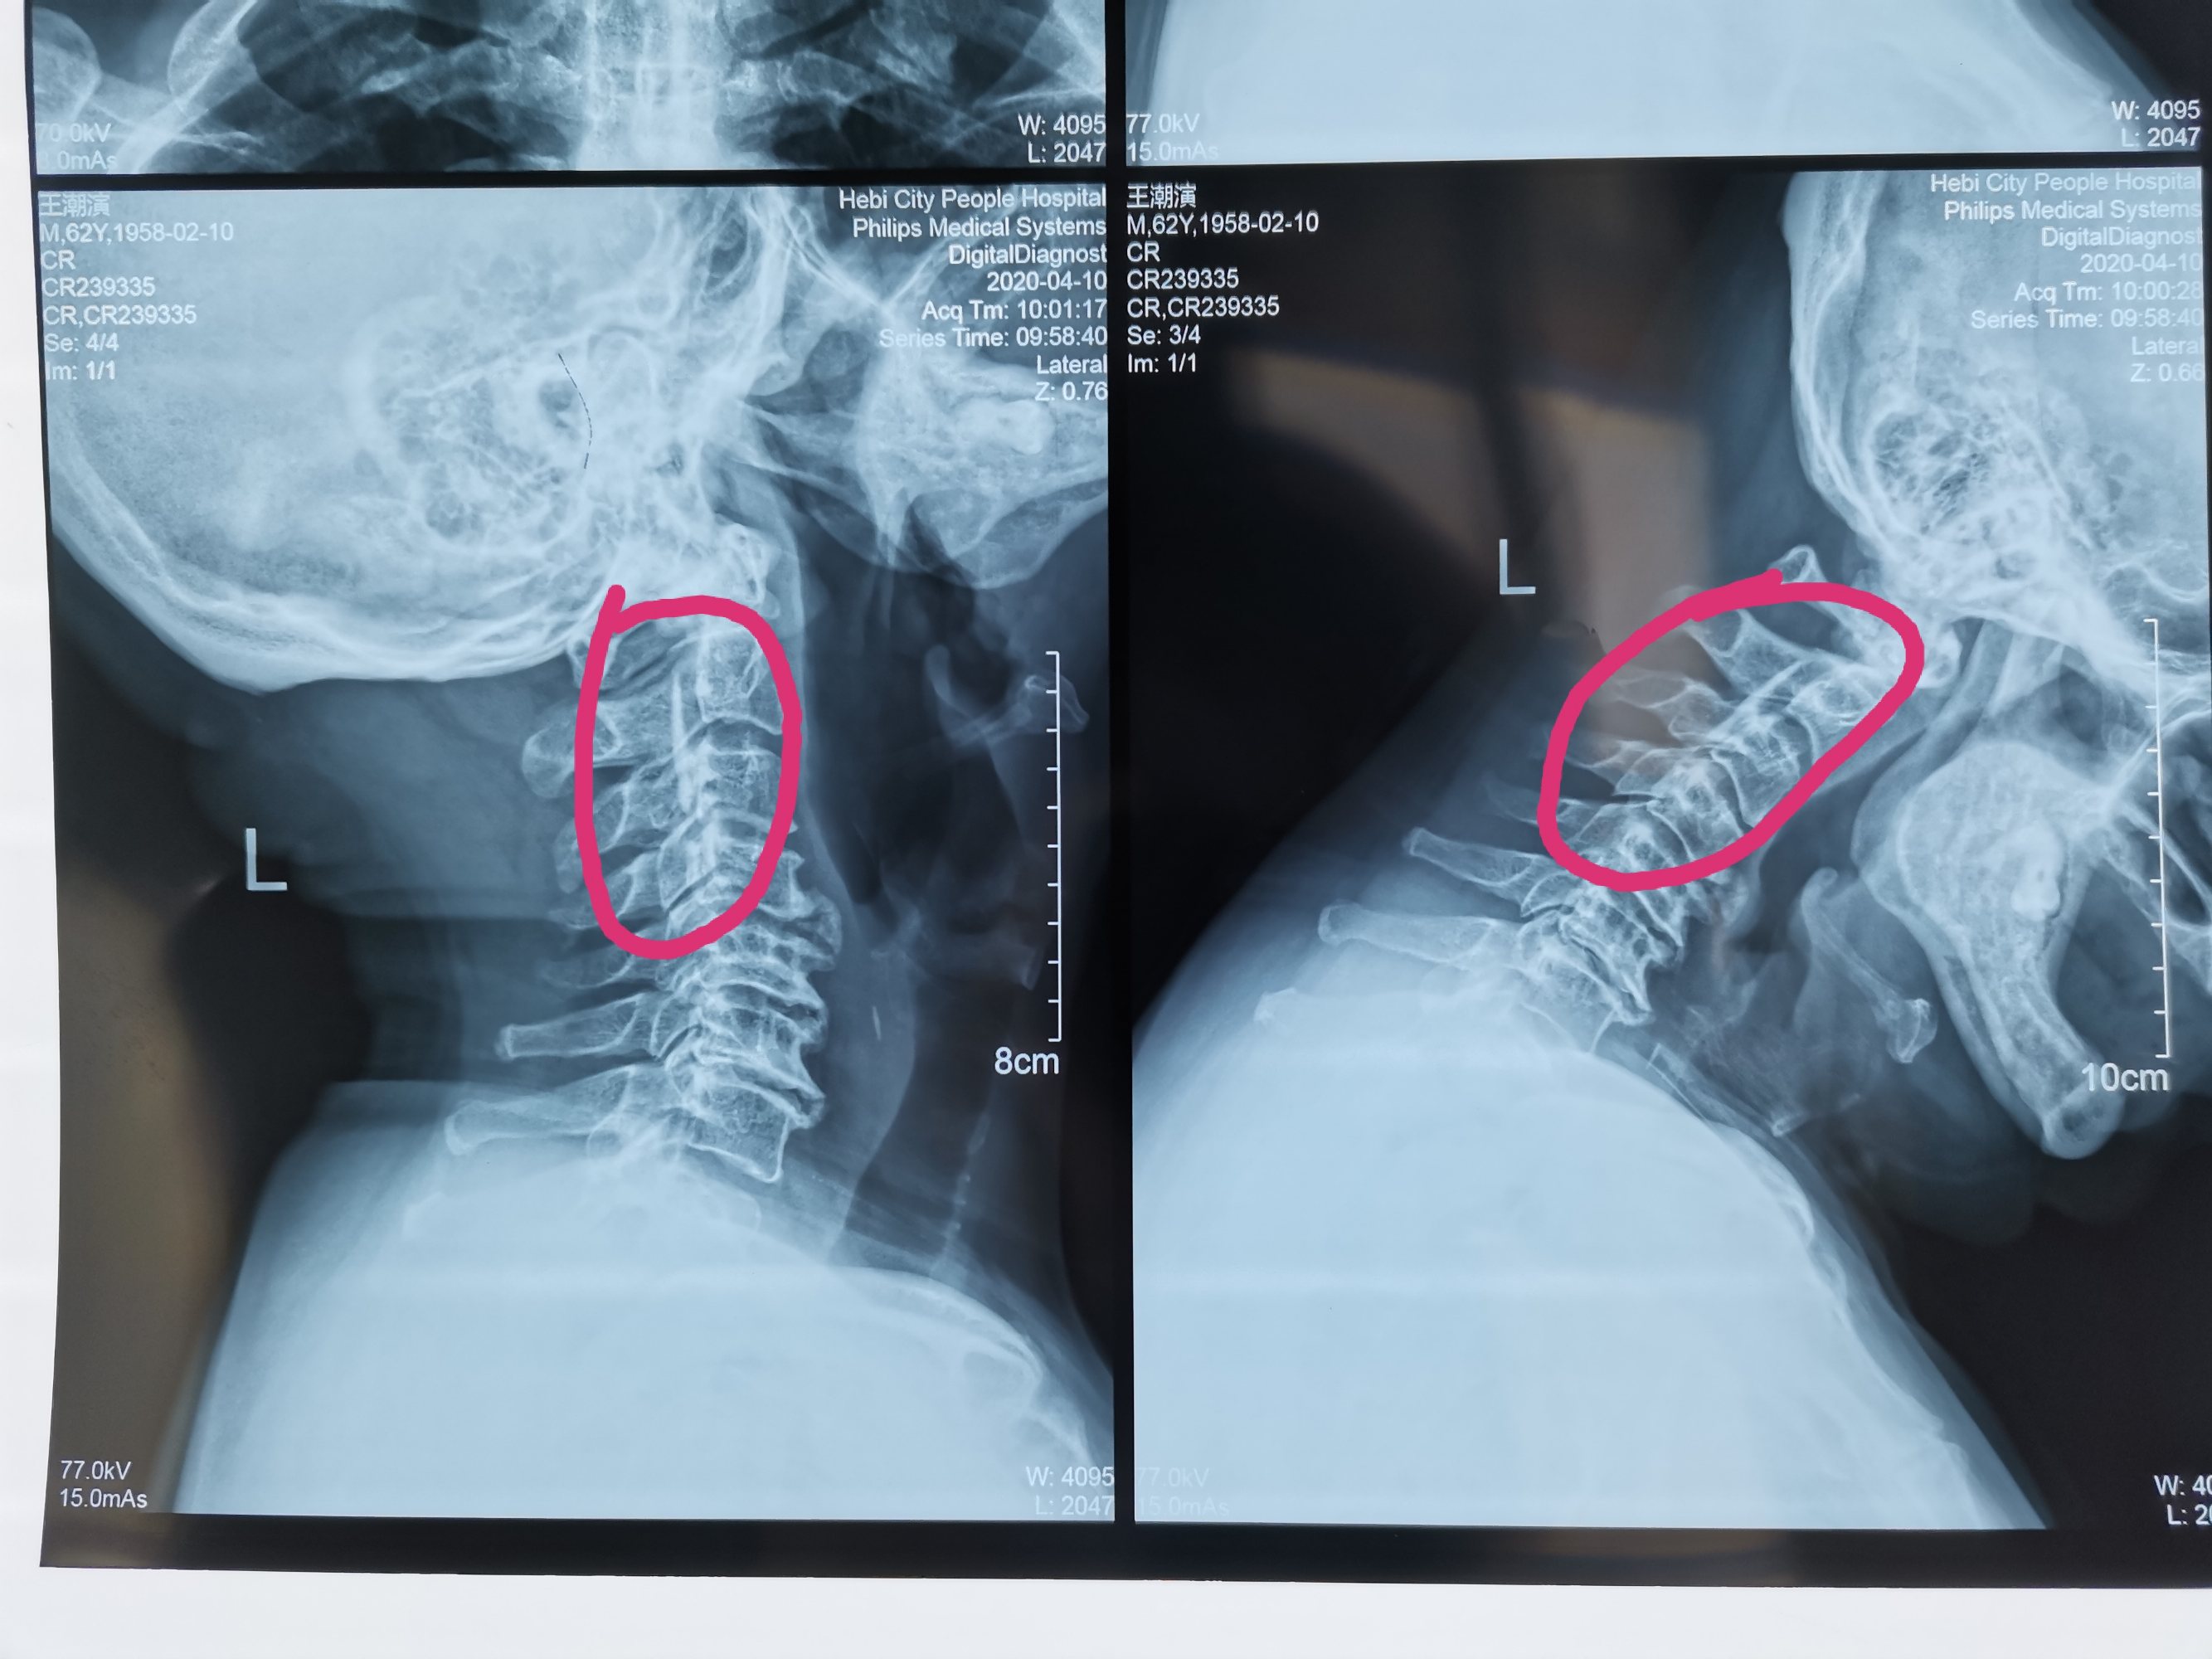

如果患者骨质增生较为严重,出现压迫神经的现象,可能会导致患者发生颈背疼痛、四肢无力、手指发麻、行走困难 背疼痛、四肢无力、手指发麻、 以及头晕恶心的症状;如果患者的椎动脉受到了压迫,那么患者的睡眠质量就会下降,导致患者的心情和精神都受到了影响,所以颈椎骨质增生的危害很大;如果增生组织对于神经根的压迫非常严重甚至可能导致患者发生瘫痪的严重后果。

通过以上介绍可以看出颈椎骨质增生对于患者的健康有着较为严重的威胁。一旦发生了常见的颈椎骨质增生的症状务必积极的去医院检查治疗。对于一些骨质增生并不是非常严重的患者,建议使用中医方法治疗;对于一些非常严重、病史较长的颈椎骨质增生患者建议采取手术治疗的方法。治疗的过程中还应该根据自己的情况制定科学有效的颈椎护理工作,日常养成良好的工作、生活习惯,如此多多管齐下,才能更好地治疗颈椎骨质增生,避免严重的疾病危害发生。